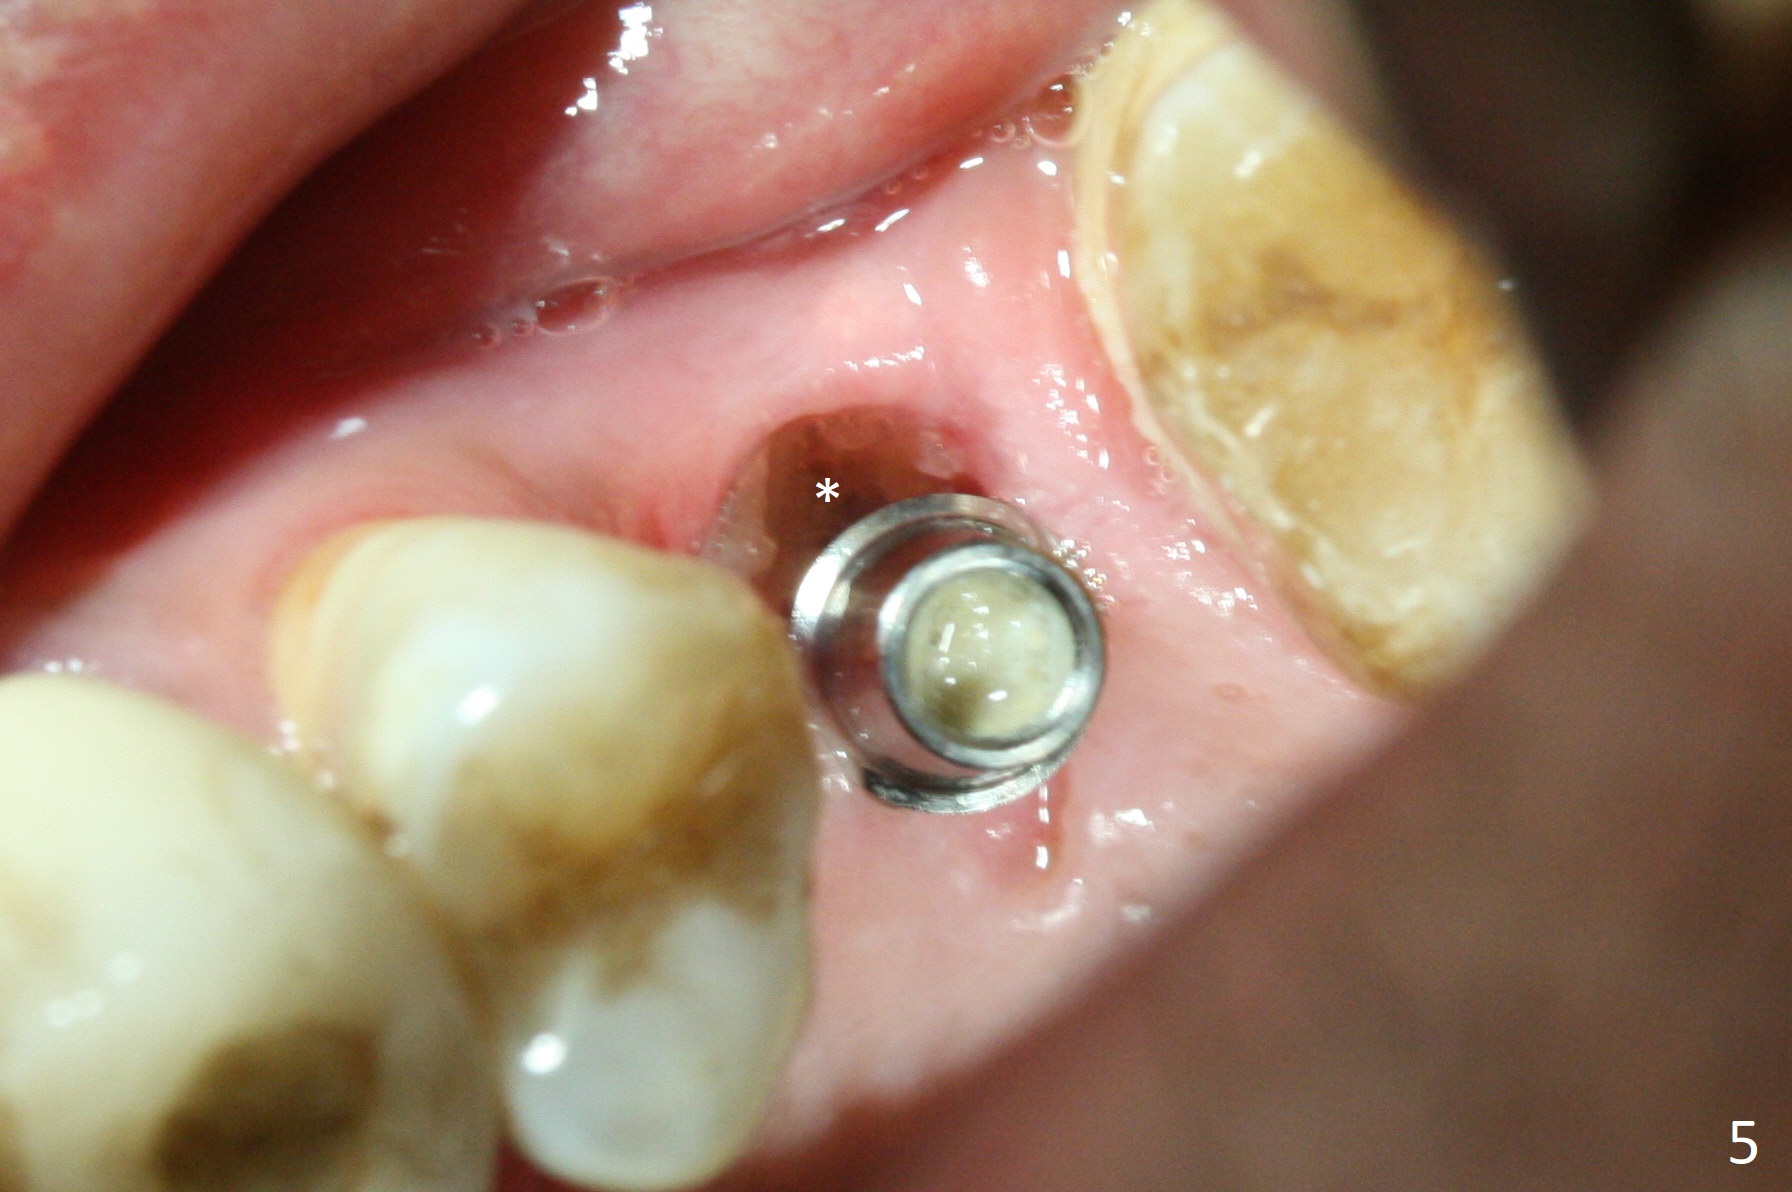

Osteotomy is initiated with Magic Split and 3 mm Magic Expander (ME, flapless) nearly 3 months post socket preservation. To improve the trajectory, the ME is redirected (Fig.1 red line). After use of 3.8 mm ME, Vanilla Graft is placed in the buccal and mesial aspects of the osteotomy. Following reuse of 3 and 3.8 mm MEs, a 4x11 mm dummy implant is inserted with stability (Fig.2 (*: allograft)). More of allograft is placed prior to placement of 5x11 mm IBS implant (Fig.3,4 (~30 Ncm)). The latter is placed palatal. Last the allograft is placed palatal. A 5x4(2) mm abutment is placed to hold periodontal dressing in place. When the ridge is narrow, the implant should be small; 4 mm probably the most appropriate in this case. There is a buccal gap 2 weeks postop (i.e., after dislodgement of periodontal dressing, Fig.5). The implant and abutment appear to be loose ~ 1.5 months postop. The pair abutment is changed to a healing one (5x3mm). The implant seems to be osteotointegrated 3.5 months posotp (Fig.6). Because of the mesial shift of the tooth #15 (Fig.6 arrow (6 months post #14 extraction; anterior open bite)), an angled abutment (5x4mm, 15 degree) is used (Fig.7). Limited orthodontic treatment has to be initiated because the mesially shifted #15 has no occlusal contact mesially (Fig.7 *). A provisional is fabricated with light supra-occlusion. A separator is placed between #14 and 15. Once a space is created in a week, acrylic is added to the distal surface of the provisional and the separator is re-used. In fact the implant is found to be unstable 4.5 months postop (Fig.8,9). The palatal (P) plate is thin and incomplete. The provisional is reduced infraocclusal. Two months the implant remains unstable and is removed.